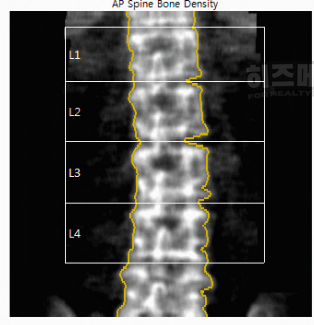

검사 대상 부위로는 주로 허리뼈와 고관절을 측정합니다. 허리뼈는 L1에서 L4까지의 네 개의 요추를 중심으로 검사하며, 이곳은 체중을 많이 받는 부위라서 뼈 상태를 잘 보여줍니다. 고관절은 대퇴골 경부와 대퇴골 전체를 측정합니다. 고관절은 체중의 대부분을 받는 부위로, 나이가 들수록 약해지기 쉽기 때문에 뼈 밀도를 측정할 때 매우 중요한 부위입니다.

1) 요추(L1-L4)

허리뼈 중에서 L1부터 L4까지의 네 개 요추가 골다공증 검사에 사용됩니다. 이 네 개의 요추는 서로 연결되어 있고, 체중을 많이 받기 때문에 뼈 밀도를 확인하기에 좋은 부위입니다.

그런데 L5는 보통 검사에서 제외합니다. L5는 골반에 가까워 다른 요추와 다르게 구조적으로 영향을 받아 결과에 차이가 있을 수 있기 때문입니다. 검사 결과의 일관성을 위해 L1-L4만 사용하는 것이 일반적입니다.